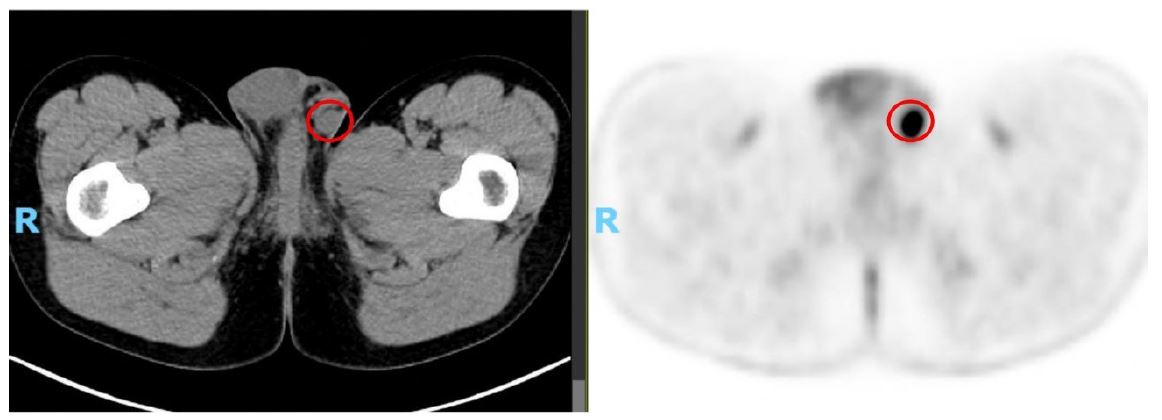

Given persistent respiratory symptoms without evidence of infection, a chest Computed Tomography (CT) scan was conducted, revealing a solid lesion in the right lower lobe suggestive of a primary tumor, accompanied by bilateral hilar lymphadenopathies. Subsequent Positron Emission Tomography-Computed Tomography (PET)-CT demonstrated elevated metabolic activity in the pulmonary lesion, bilateral hilar, cervical, mediastinal, and left inguinal lymphadenopathies, and a probable metastatic left scrotal lymph node (Figure 2).

Figure 2: The left image presents a CT scan revealing a right testicular nodule, while the right image shows the corresponding PET scan, which exhibits increased metabolic uptake at this site, consistent with malignancy.

At the first reassessment after four cycles of selpercatinib, a response was observed, marked by a significant reduction in tumor mass and disease stability confirmed by subsequent imaging (Figures 4 & 5).

Figure 5: The left image depicts the testicular lesion at diagnosis (May 2023), while the right image illustrates its resolution following 13 cycles of selpercatinib (January 2025).